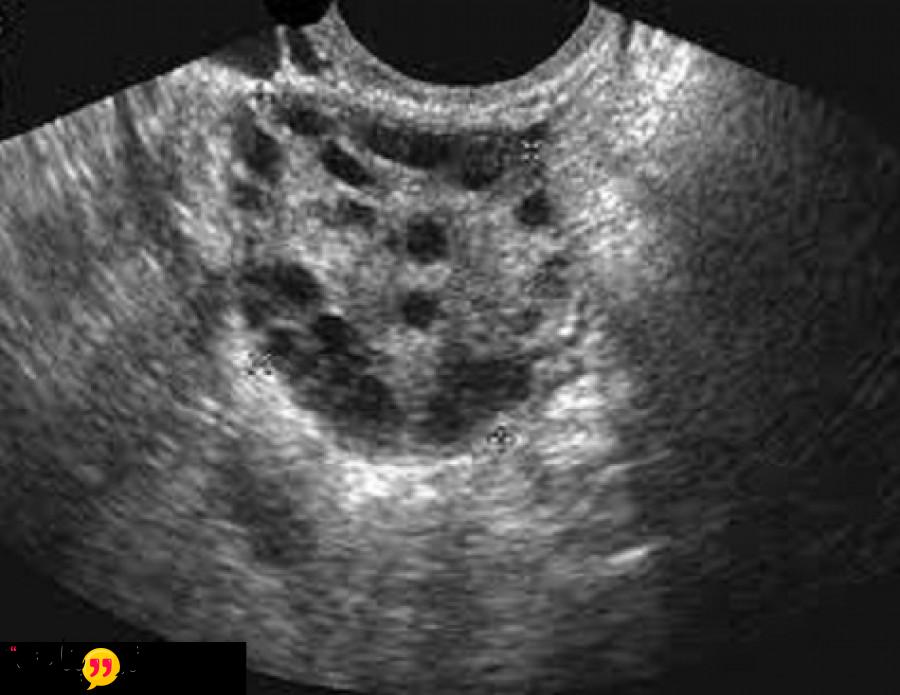

أشعة الرنين المغناطيسي للمبايض : تعتبر أشعة الرنين المغناطيسي من المجالات الطبية الحديثة , فهو عباره عن جهاز كبير جدا يقوم بأخذ لقطات من داخل المنطقة التي يعاني منها المريض , فهذه الاشعة يمكن أجرإها علي المخ او الرحم او القدمين أو الذراعين او المبيض او اي شئ في الجسم , يتكون جهاز الرنين من انبوبة دائرية كبيرة محاطة بالمغناطيس ويستلقي المصاب او المريض علي سرير صغير داخل الجهاز ليقوم باجراء الاشعة .

- تقوم هذه الاشعه بتصوير ادق التفاصيل الموجوده في الجسم ولكن لا تستخدم اشعة الرنين في جميع الحالات المرضية .